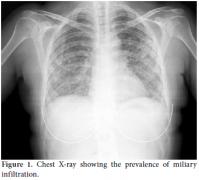

The polymerase chain reaction (PCR) tests for TB and cytomegalovirus (CMV) were negative, and the BAL specimen cultures were negative for bacterial, fungal, and mycobacterial infection. Cranial CT showed hyperdense mass lesions, and contrast-enhanced cranial magnetic resonance imaging (MRI) detected multiple hypodense nodular lesions that were abscess-like (Figure 2) and ring enhancing in the frontal mesencephalon region and cerebella regions. The results for toxoplasma immunoglobulin (Ig) M and IgG were also negative. Based on these findings, the patient's treatment was changed to linezolid and ceftriaxone. One month later, the patient's dyspnea had improved, and the lung infiltration was reduced. The patient was then discharged from the hospital with a prescription for oral TMP-SMX and cefixime treatment; however, a week later, she was readmitted with increased dyspnea and a 38.5 °C fever. On admission, we observed a seizure and left-sided hemiparesthesia; hence, linezolid, ceftriaxone, levetiracetam, and phenytoin were started. Cranial MRI showed a progression of the abscess lesions, especially in the right frontal region (2.5 cm diameter) and midline shift of the ventricle; therefore, urgent surgical decompression of the abscess was performed. A post-surgical examination of the blood cultures was performed at a private laboratory, and it showed Nocardia farcinica (N. farcinica) infection via a sequencing analysis of the 16S rRNA gene of isolates. The N. farcinica antibiogram was resistant to TMPSMX, ampicillin, and imipenem, so metilmicin was added to the patient's treatment. A good outcome was achieved following three months of intravenous treatment as the patient's brain abscess regressed. However, the left hemiparesis persisted.